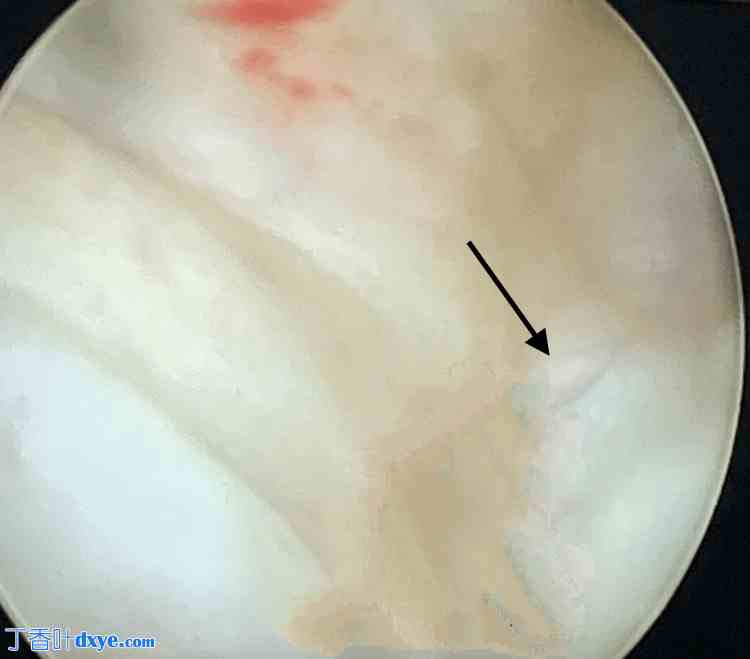

使用F-20膀胱镜进行膀胱镜检查以进行诊断评估。诊疗结果显示,输尿管间基底部近端存在一个1×1.5 cm的三角上膀胱阴道瘘(VVF),如图1所示。因此,确诊为子宫切除术后VVF。

图1. 使用F-20鞘管进行膀胱镜检查。

黑色箭头:1×1.5 cm的三角上膀胱阴道瘘